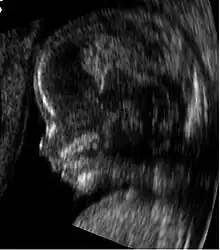

Fetus at 14 weeks (profile)

Obstetric sonography is useful in the assessment of the cervix in women at risk for premature birth. A short cervix preterm is associated with a higher risk for premature delivery: At 24 weeks' gestation, a cervix length of less than 25 mm defines a risk group for spontaneous preterm birth. Further, the shorter the cervix, the greater the risk.[19] Cervical measurement on ultrasound also has been helpful to use ultrasonography in patients with preterm contractions, as those whose cervical length exceeds 30 mm are unlikely to deliver within the next week.[20]